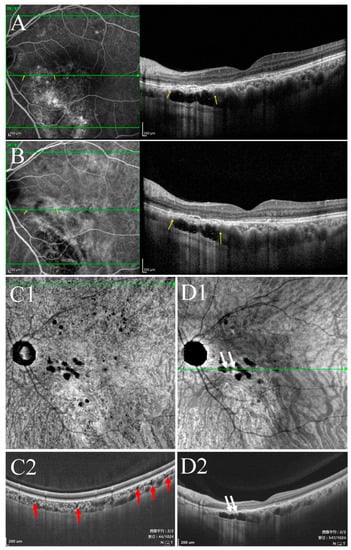

- Type II were large, usually isolated and in the Sattler’s and Haller’s layers. Depending on the overall choroidal thickness of the patients, the upper margin was around 100~200 μm below the BM and the lower margin was around 200~400 μm below the BM (Figure 4).